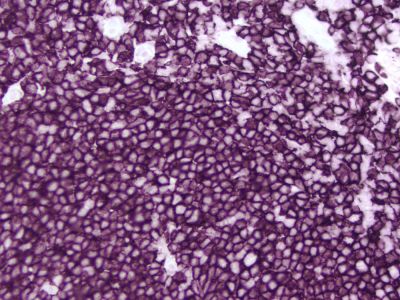

The peroxidase micropolymers of the ImmPRESS HRP polymer reagent limit steric interference and provide enhanced accessibility to the target, avoiding the disadvantages of other polymer systems that use large dextrans or other macromolecules as backbones. The result is crisp, strong staining of antibody targets, especially nuclear and membrane antigens (such as Ki67, estrogen receptor, bcl-2, CD3, CD8 and CD10) and greater sensitivity than other polymer systems.

The staining procedure is simple as shown in the diagram below. Following a blocking step with the diluted normal horse serum, sections are incubated with primary antibody. After a brief wash, the appropriate ImmPRESS Reagent is added to the sections and incubated for 30 minutes. Sections are again rinsed and the slides are developed with the peroxidase substrate of choice.